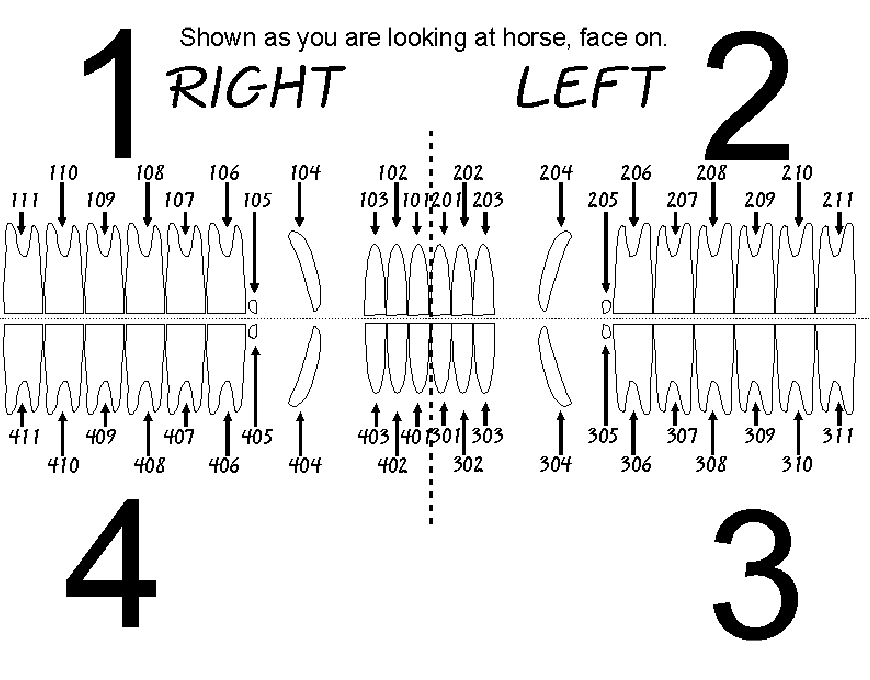

dental anatomy- triadan system

1-upper right

2-upper left

3- lower left

4-lower right

x01= first incisor

x04= canine

x05= wolf tooth

x08= last premolar

x09= first molar